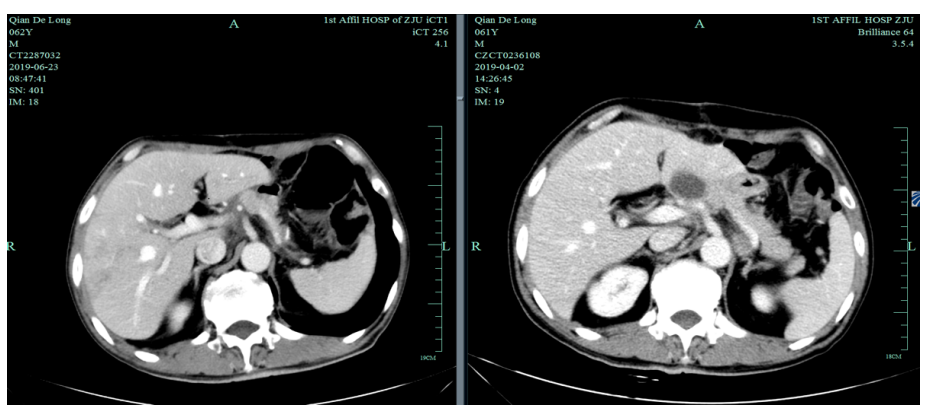

一线化疗疗效评估(2019.6 vs 2019.4):胃癌术后改变。影像评估CR。

影像学评估:胃癌术后改变。持续CR。

2020-11-3全腹部CT平扫+增强提示胃癌术后改变,术周及腹膜后多发肿大淋巴结显示,对照2020-7-7CT淋巴结肿大进展,结合临床疗效评估PD。